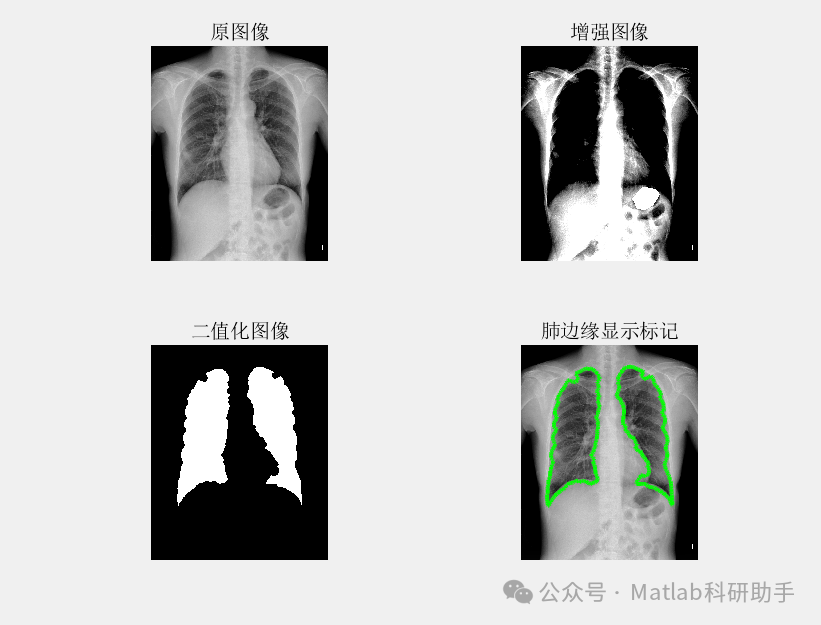

⛳️ 运行结果